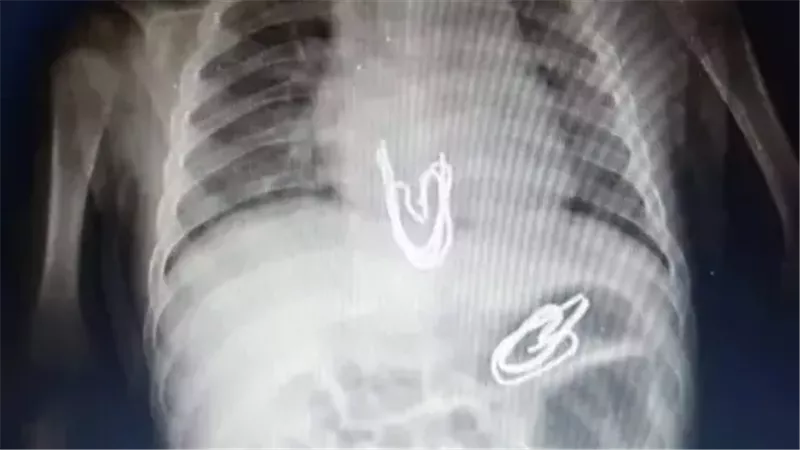

نجاح طبي بسوهاج الجامعي.. استخراج دبوس من معدة طفل دون جراحة

شهد مستشفى سوهاج الجامعي إنجازًا طبيًا جديدًا يُضاف إلى سجل نجاحاته في رعاية الأطفال، حيث تمكن فريق طبي متخصص من وحدة أمراض الجهاز الهضمي والكبد ومناظير الأطفال بقسم طب الأطفال من إجراء تدخل دقيق لاستخراج جسم غريب من معدة طفل يبلغ من العمر 4 سنوات، باستخدام منظار معدة مخصص للأطفال، دون الحاجة إلى تدخل جراحي، ووسط إجراءات دقيقة وآمنة.

وبحسب ما أعلنه المستشفى، فإن الحالة لطفل ابتلع دبوسًا معدنيًا، ما استدعى تدخلاً عاجلاً لإنقاذه. وبالفعل، نجح الفريق في استخراج الدبوس عبر المنظار، في إجراء استغرق وقتًا قصيرًا، دون حدوث أية مضاعفات أو آثار جانبية، ليغادر الطفل المستشفى بعد ثلاث ساعات فقط، وهو في حالة صحية مستقرة.